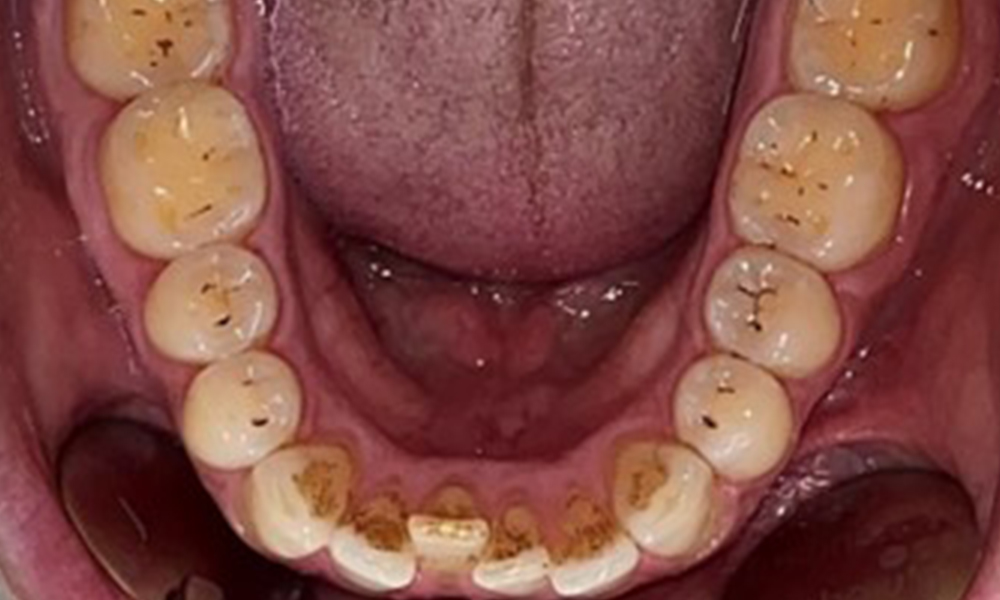

Occlusal view of the mandible.

Fig. 4: Occlusal view of the mandible, © Dr R. Krapf

The patient has full dentition with a total of 28 teeth. There were noteworthy erosions and attritions. (Fig. 4, Fig. 5). Due to bruxism, the patient has been wearing a splint with an adjusted bite block at night for many years. The erosions were caused by long-term consumption of isotonic beverages. No periodontal bone loss or active caries were observed.